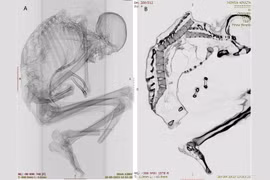

(Kiến Thức) - Được tìm thấy tại Gebelein, Ai Cập, xác ướp người đàn ông tóc vàng gây chú ý khi ở trong tư thế bào thai. Một số bí mật về thi hài người đàn ông qua đời hơn 5.000 năm trước được giới chuyên gia tiết lộ.

(Kiến Thức) - Được tìm thấy trong thung lũng sông Nile, Ai Cập, Gebelein Man A hay còn gọi Ginger là xác ướp tự nhiên nổi tiếng thế giới. Nhờ thi hài nguyên vẹn, các chuyên gia giải mã nhiều bí mật, bao gồm những hình xăm cổ.